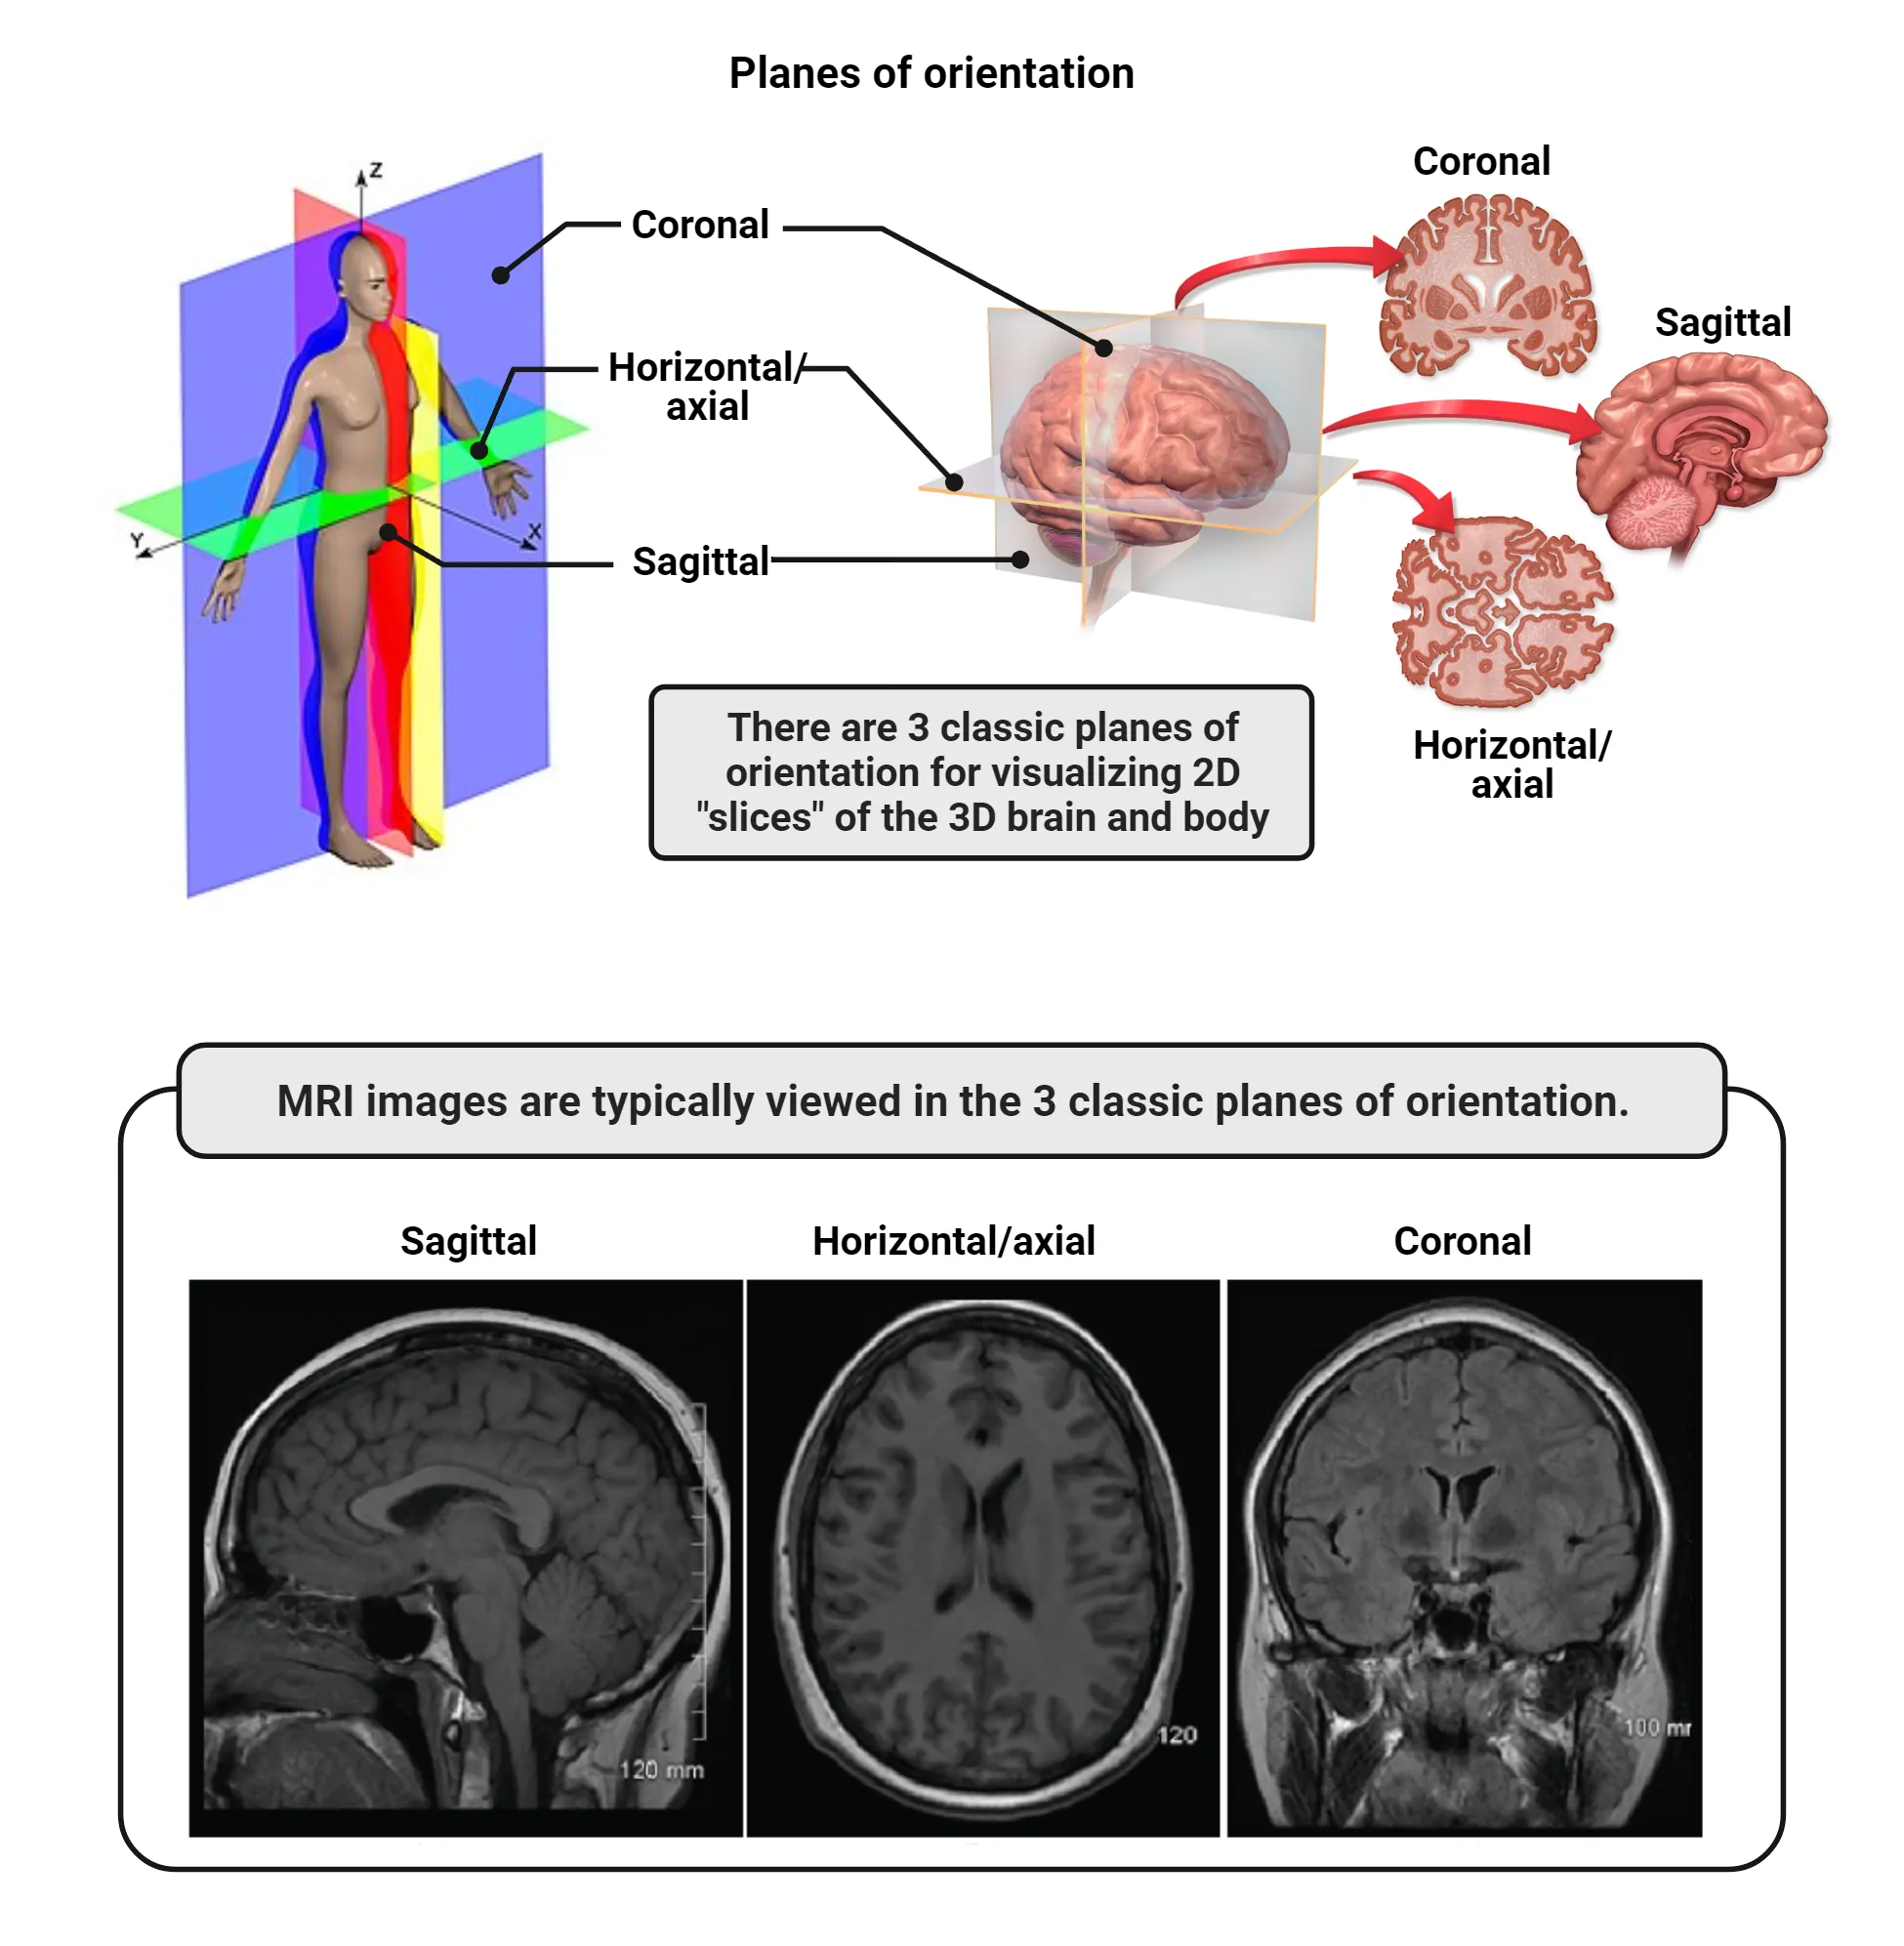

There are three planes for sectioning the brain for anatomical analysis: coronal sectioning (cutting the brain front to back); sagittal sectioning (cutting the brain left to right) and horizontal or axial sectioning (cutting the brain top to bottom) (Figure 1.23).

Diagrams of major anatomical planes. A human body sectioned in 3D with horizontal, coronal and saggital planes are shown. The human brain also shows 2D slices of each plane. Below, MRI images of slices of each plane are shown.

Figure 1.23 Planes of orientation Image credit: 3D human body with planes adapted from: By David Richfield and Mikael Häggström, M.D. and cmglee - Human anatomy planes, labeled.jpg, CC BY-SA 4.0, https://commons.wikimedia.org/w/index.php?curid=91212408. 3D brain with planes adapted from: By Blausen.com staff (2014). Medical gallery of Blausen Medical 2014;. WikiJournal of Medicine 1 (2). DOI:10.15347/wjm/2014.010. ISSN 2002-4436., CC BY 3.0, https://commons.wikimedia.org/w/index.php?curid=31118590. MRI images from: Kumar & Dhurn. 2016. A study of MRI segmentation methods in automatic brain tumor detection. International Journal of Engineering and Technology. CC BY 3.0.